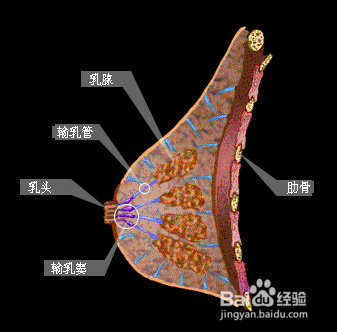

乳腺癌是女性首位或者第二位常见的恶性肿瘤了。乳腺癌好发于绝经期前后的40-60岁,偶有男性乳腺癌发生。现今社会乳腺癌的发病率也逐年增加,也越来越年轻化,据统计乳腺癌20~40岁的职业女性成为高发人群。

乳腺癌的临床症状

大多数是发现无痛性乳腺质硬包块就诊,且不活动性包块,边界不清;包块一般通过自己检查发现的,自己检查手法:用手掌面(非手指尖),对乳房外上、外下、内下、内上,最后中央乳头区域全面检查。注意:不用手指捏抓乳房组织(很多患者就是抓到包块就诊,检查其实就是乳房腺体,因为腺体本来就是一个一个排列的,这样很不准确)。